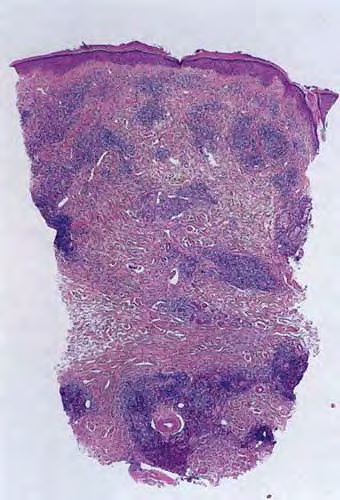

Atlas of skin histopathology

Arthropod bite = عضة مفصليات الأرجل